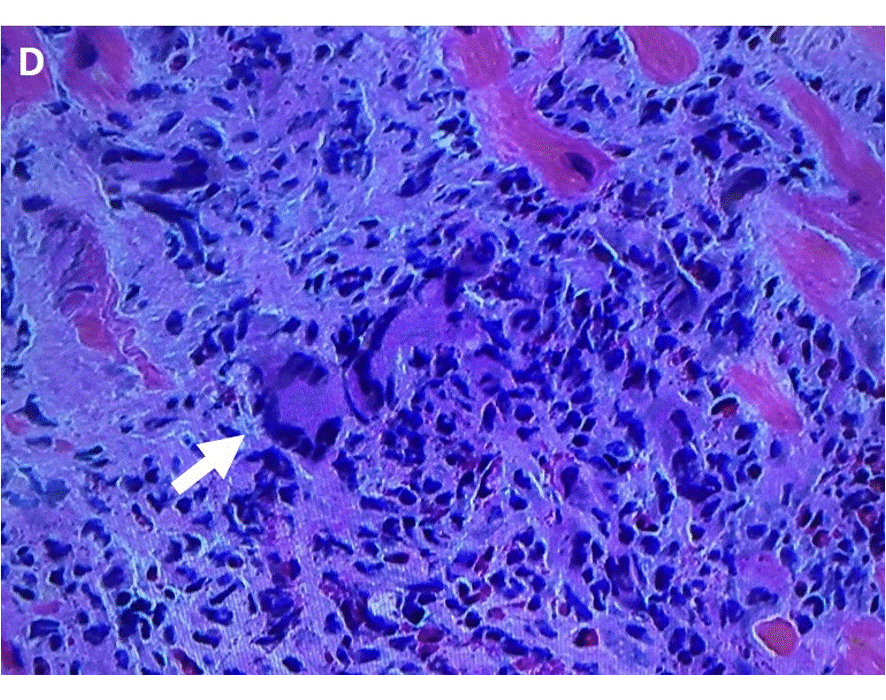

Cardiac MRI (cMRI) demonstrated late gadolinium enhancement (LGE) in the right ventricular aspect of the interventricular septum on T1 sequences not confined to a typical coronary territory. Positron emission tomography (PET) with fludeoxyglucose (18F-FDG) showed increased avidity in the same region without extracardiac uptake. A coronary computed tomography (CT) angiogram also showed decreased attenuation of the same region without CAD or coronary anomalies. Pathology from an endomyocardial biopsy showed dense lymphocytic and eosinophilic infiltrate with multinucleated giant cells without granulomas, consistent with GCM.

GCM requires prompt diagnosis and treatment to prevent mortality and morbidity. While endomyocardial biopsy remains the gold standard for diagnosis, non-invasive imaging allows for earlier diagnosis and assessment of response.